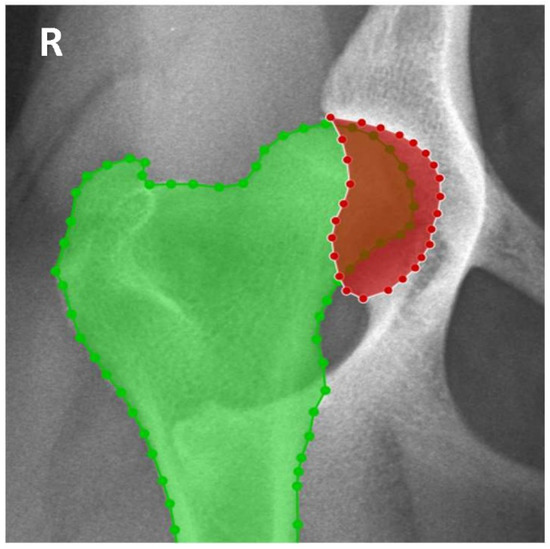

2.1. Radiographic Measurements

- Da Silva, D.M.; Filipe, F.; Franco-Gonçalo, P.; Colaço, B.; Alves-Pimenta, S.; Ginja, M.; Gonçalves, L. Semantic Segmentation of Dog’s Femur and Acetabulum Bones with Deep Transfer Learning in X-ray Images. In Proceedings of the 21st International Conference on Intelligent Systems Design and Applications (ISDA) 2021, Online, 13–15 December 2021; Lecture Notes in Networks and Systems. Springer: Cham, Switzerland, 2021; Volume 418, pp. 461–475. [Google Scholar] [CrossRef]